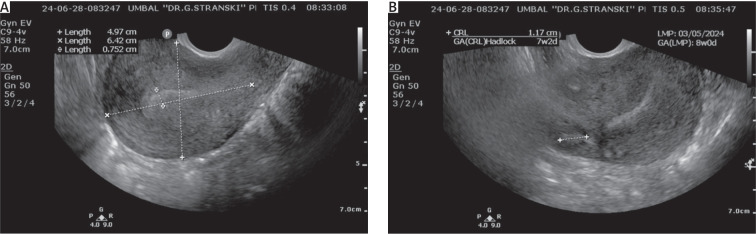

Interstitial pregnancy (IP) is a rare kind of tubal pregnancy, which occurs in 2-4% of all ectopic pregnancies. It occurs as a result of implantation of the gestational sac in the proximal intramural part of the fallopian tube. Risk factors include the following: pregnancy conceived after assisted reproductive technologies, ipsilateral salpingectomy, previous ectopic pregnancy, congenital tubal and uterine malformations, pelvic inflammatory disease, and the presence of an intrauterine device. Given the rare and complex nature of interstitial pregnancies, diagnosis and management are difficult. Transvaginal ultrasound is the most specific instrumental method for early diagnosis that can decrease possible complications, such as rupture, severe haemorrhage, and risk of future infertility in the case of misdiagnosis. There are various surgical and non-surgical methods for the treatment of interstitial pregnancy. The method of choice depends on gestational age, whether the pregnancy is intact or ruptured, and the patient's desire for future fertility. However, surgery is still the main option for the treatment of IP because it offers definitive treatment. Generally, complicated IP is associated with high rate of mortality due to delayed diagnosis and treatment. We present a case report related to a multiparous woman with amenorrhoea and ultrasound findings corresponding to sonographic criteria for interstitial pregnancy. Laparoscopy was performed, which confirmed the diagnosis. Bilateral salpingectomy and right cornual resection were performed because the patient had no intention for future pregnancies.